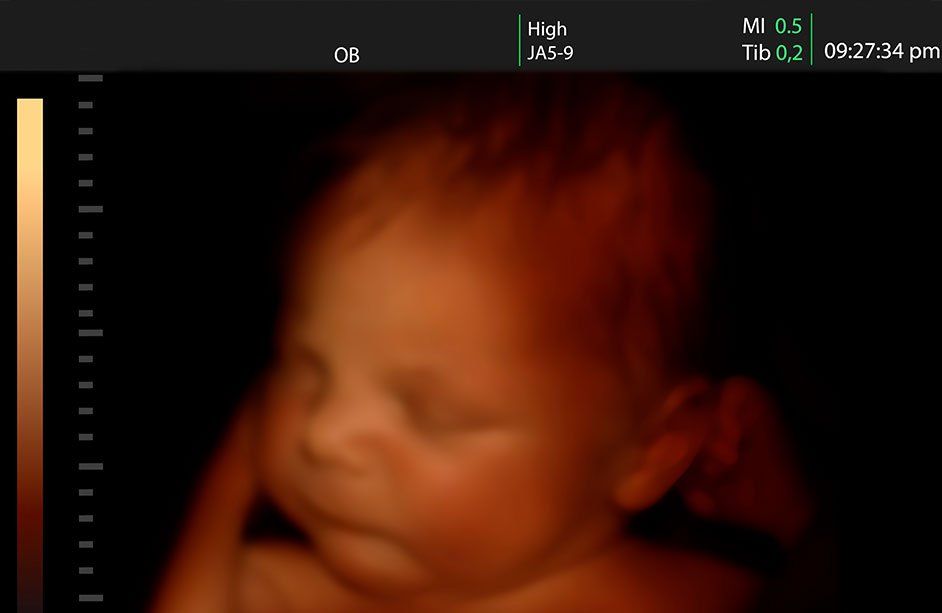

- Imágenes en 3D-4D: Valoración de la anatomía facial y corporal del bebé: movimientos, parpadeo de los ojos, deglución de líquido amniótico, juego con sus manos. Primera foto del bebé dentro del útero. Imágenes en 3D-4D. Video de la ecografía en DVD. Fotos de la ecografía en CD.